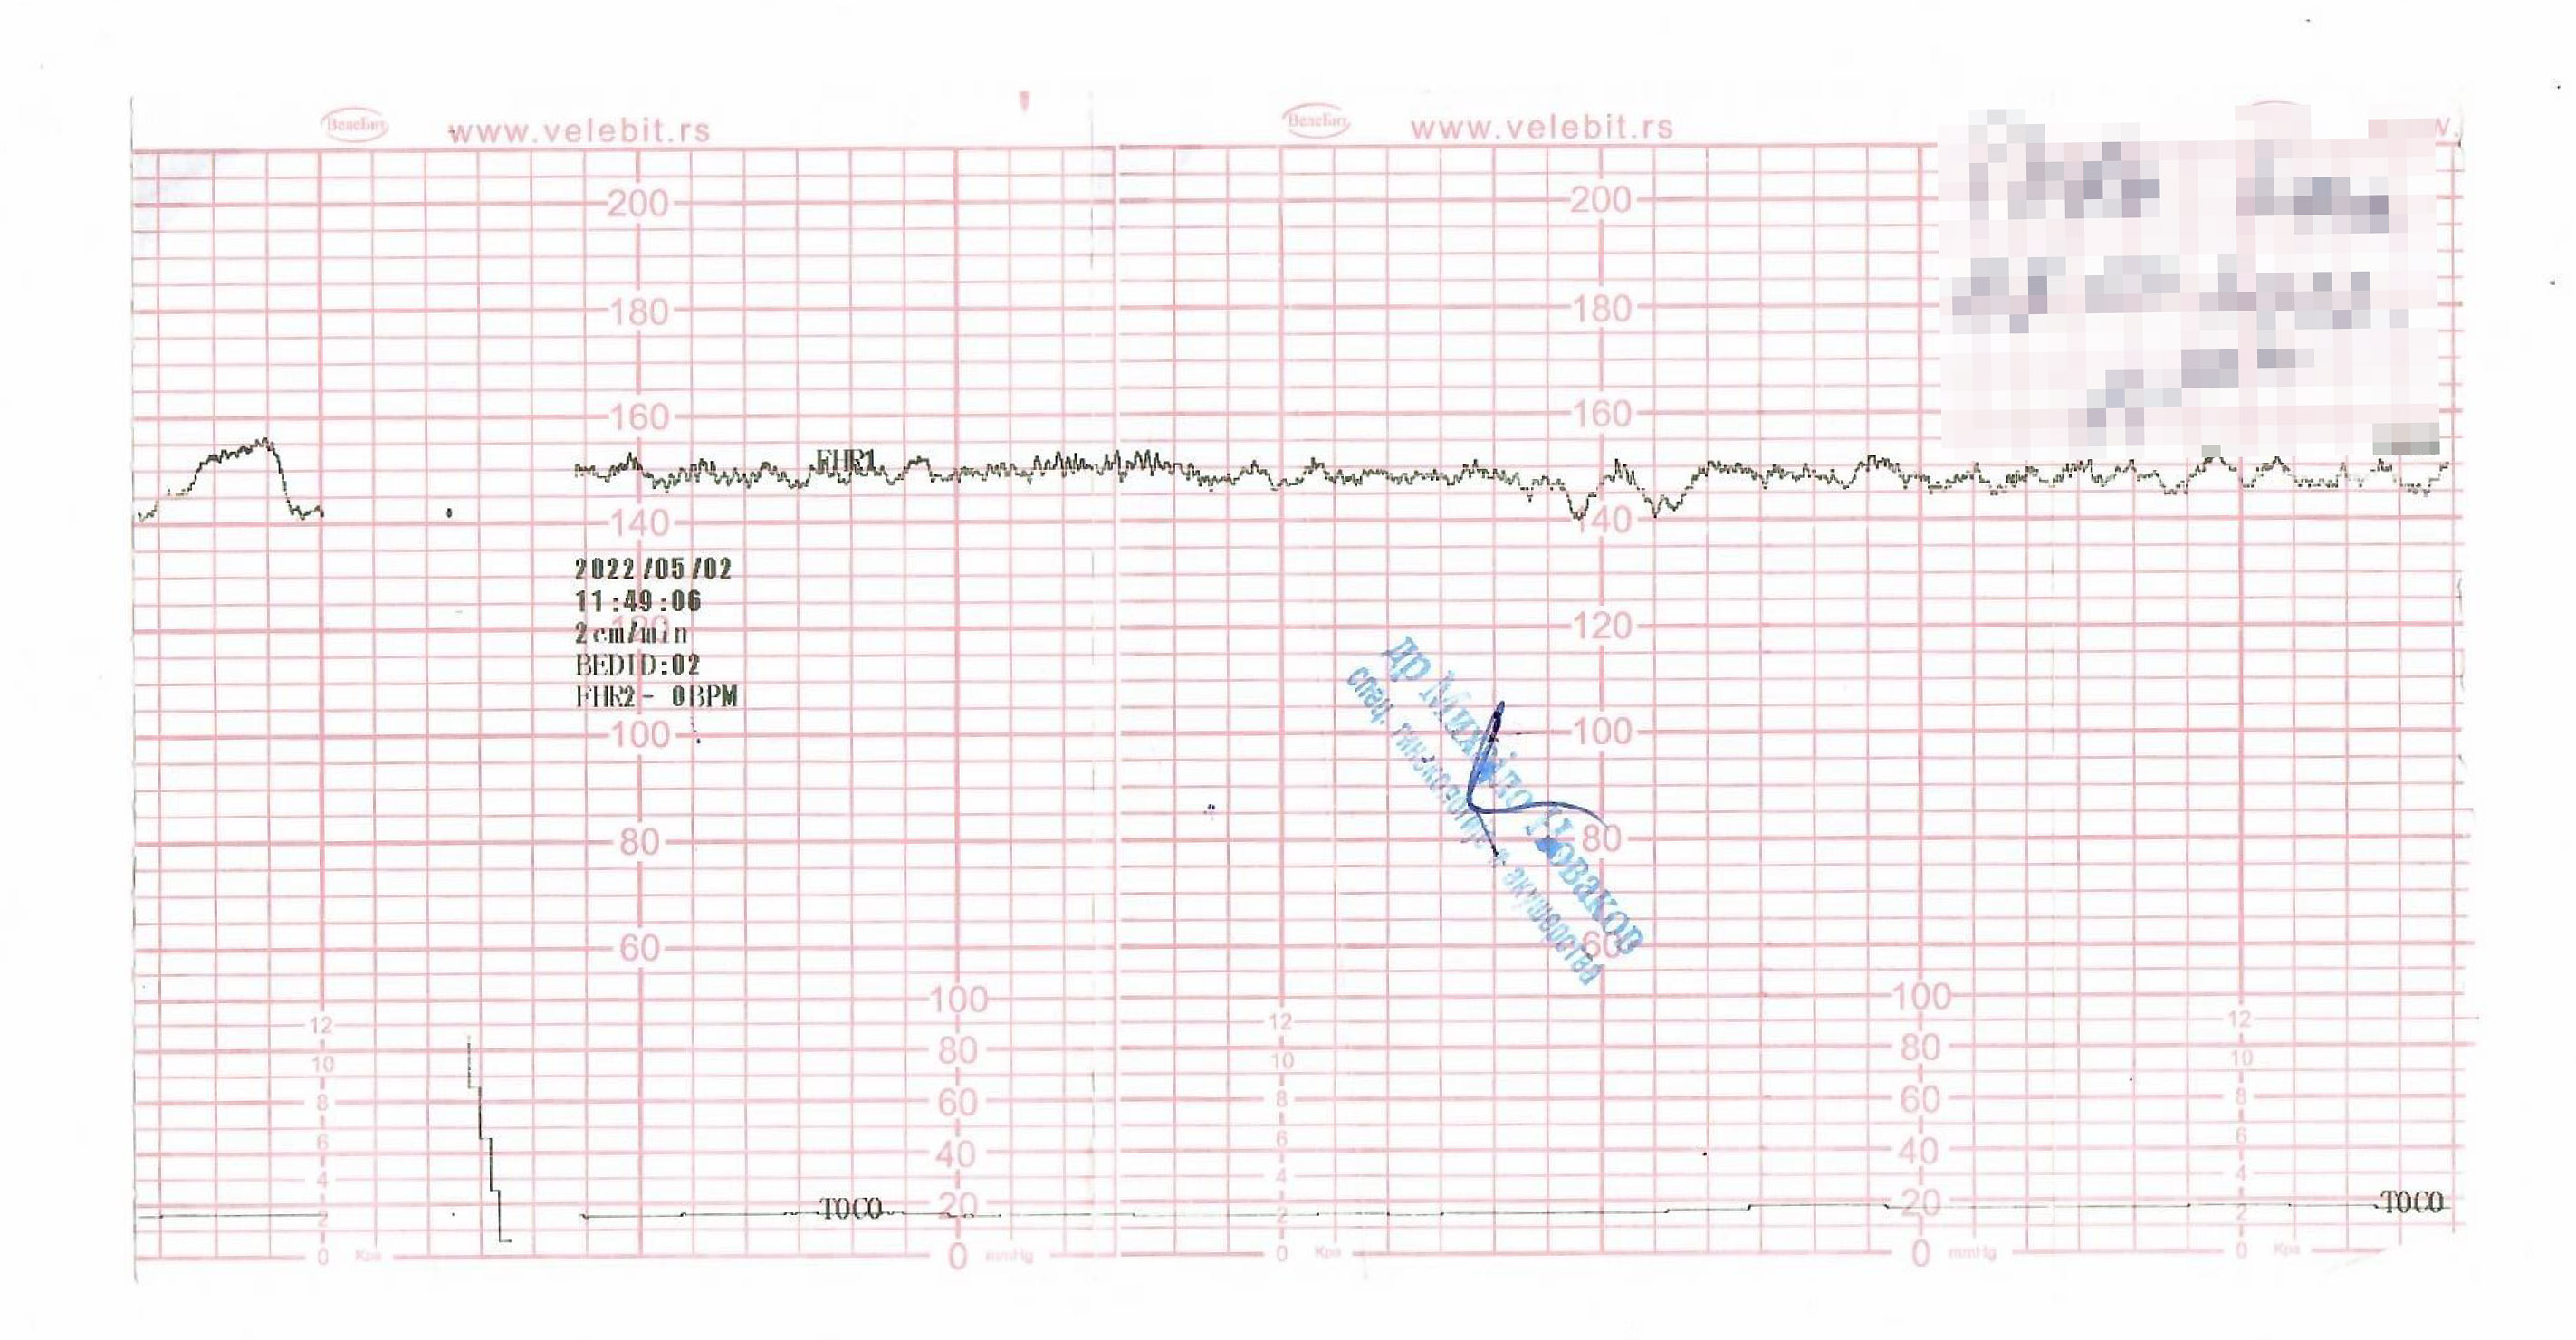

Foto: Goran Srdanov, Privatna arhiva Ivana je četiri dana nosila preminulo dete u stomaku, lekari joj rekli da ide kući jer "beba spava": “Samo sam plakala, a oni nisu ništa preduzeli” autor: Ana Marković Društvo 03. apr. 2026. 19:05 0 Podeli vest: Ivana Torda (38) iz Pančeva doživela je stravičnu tragediju pre četiri godine, kada je izgubila bebu, nakon što su je iz pančevačke bolnice, 2. maja 2022. kada je bio porođajni termin, vratili kući, uz reči da njena “beba spava”. Rečeno joj je tada da dođe za dva dana. Kada se Ivana vratila, 4. maja, posle pregleda, lekari su joj saopštili da je njena beba umrla u stomaku još pre 48 sati. Ivana je tada podvrgnuta, kako za Nova.rs kaže, agresivnim metodama izvlačenja bebinog tela iz stomaka, zbog čega je kasnije završila u KBC Dr Dragiša Mišović na operaciji. Zaključak veštaka Medicinskog fakulteta u Beogradu, pokazao je da lekari nisu postupili po propisima, a Ivana i njen suprug Boris, do danas se bore sa traumom koju su preživeli. Podeli vest: Oglas Početkom 2022. godine Ivana se sa suprugom Borisom iz Češke preselila u Srbiju, kada je bila u prvim mesecima trudnoće. Na preglede je, sve do termina za porođaj, odlazila privatno u ordinaciju u Pančevu, kod ginekologa V. P., a kada je došao porođajni dan, lekar je, kako je ispričala za naš portal, uputio u Opštu bolnicu Pančevo. Tog dana više puta radili su joj CTG, jer očigledno nešto nije bilo u redu. Međutim, Ivanu su poslali kući i rekli joj da se vrati za dva dana jer joj beba spava i ne mogu da je probude. Zapravo, kako ona kaže, nisu čuli otkucaje srca, beba se nije pomerala, a ubrzo je, nažalost, saznala i zašto. Foto: Privatna arhiva “Bila je to moja prva trudnoća. Iz Češke smo se preselili u Srbiju kako bih se ovde porodila. Odlučila sam da trudnoću vodim privatno kod doktora V. P. On me je i poslao da se porodim 2. maja u pančevačku bolnicu, kada je bio termin. Dežurni doktor tog dana bio je M. N. koji me je, koliko sam ja kao laik mogla da primetim, vrlo traljavo pregledao. Rekao mi je da je sve u redu i da uradimo CTG. Posle me je pitao jesam li nešto jela, odgovorila sam da jesam, pa mi je rekao da pojedem nešto slatko. Posle toge je opet radio CTG. Potom mi je rečeno da se ipak vratim kući jer je beba mirna, spava i ne mogu da je probude, pa da dođem za dva dana. Tražila sam izveštaj sa pregleda, ali su odbili da mi ga daju. Iako mi je to bilo sumnjivo i nejasno, otišla sam bez izveštaja”, priča Ivana dok pokušava da zadrži suze. Prvi odlazak u bolnicu bio je u ponedeljak, a u sredu, 4. maja, ispričala je u razgovoru za Nova.rs, vratila se na porođaj, kako joj je i rečeno. Tog dana primio je novi lekar G. T. koji joj je saopštio vest, od koje se, kako kaže, i danas oporavlja. Ivana i Boris Torda Foto: Privatna arhiva “Odveli su me na odeljenje i načelnik je posle pregleda ustanovio da kod bebe nema srčane radnje. Tada mi je rečeno da je beba umrla još u ponedeljak. Bila sam u šoku. Nekoliko minuta nisam znala za sebe. Došla sam da se porodim, da donesem moju devojčicu na svet, a oni mi govore da je mrtva i da je tako mrtvu već dva dana nosim u sebi”, sada već ozbiljno uznemirena, priča Ivana. Nakon ovog užasnog saznanja, lekari su Ivanu, kako kaže, odmah poslali u porodilište na “porođaj”. "Svi su se sklanjali od mene, a ja sam samo plakala" “Spremali su me da se presvučem i probušili mi vodenjak. Niko nije hteo da me zbrine, a bilo je sigurno 15 ginekologa tamo. Ipak, svi su se sklanjali od mene. Ležala sam u bolnici sa mrtvom bebom u stomaku do sutradan. Nije bilo nikakve intervencije. Moja svekrva je onda besna otišla kod tadašnjeg direktora, koji je i sam ginekolog i zamolila ga da mi uradi carski rez i da prestanu da me muče”, naglašava Ivana. Lekari su tek četiri dana posle intrauterine smrti, prema njenom svedočenju, krenuli da vade bebu iz stomaka. “Dakle četiri dana sam nosila svoje mrtvo dete u stomaku i samo sam plakala. To je sve što sam radila, a oni su me tako ostavili. Tog četvrtog dana došao je načelnik porodilišta i rekao mi da će on to da završi, ali da su mu ‘uvalili vruć krompir’". Foto: Privatna arhiva U četvrtak, u 15 časova, Ivani su, seća se ona, uključili indukciju, a “porođaj” je krenuo tek u 23 sata. “Čekala sam gotovo devet sati. Tih dana moglo se desiti da i ja umrem zbog komplikacija. Dali su mi anesteziju i sekli mi bešiku jer nisu mogli da izvade telo bebe. Morali su da joj seku malo telo na više komada, kako bi je kompletno izvadili. To je za mene bilo previše. A to se sve dešavalo jer su predugo čekali. Načelnik je na kraju lupao glavom o zid, nije više znao šta da radi. Zbog isečene bešike, nosila sam pelene četiri meseca nakon te agresivne intervencije. Lečila sam se u KBC Dr Dragiša Mišović, gde su me operisali”, seća se Ivana sa bolom u duši. U toj bolnici su joj, kako kaže, "spajali bešiku". “Otvarali su me od pupka do vagine. Bilo je strašno, ali morali su, jer su me u Pančevu unakazili”, naglašava ona. Pročitajte još: Smrt u našim porodilištima i život na aparatima Priča se 1 Beba umrla na porođaju: Doktor dobio godinu dana kućnog zatvora Hronika 0 Slučaj koji je potresao Srbiju: Roditelji za smrt novorođenčeta optužuju šabačko porodilište, iz bolnice tvrde da je sve bilo u redu Društvo 0 Veliku podršku tokom najtežih dana, pružao joj je suprug Boris, koji se i dalje zajedno sa njom bori za pravdu zbog izgubljenog života njihove ćerkice. “Hteli smo da tužimo bolnicu, ali nismo psihički i emotivno u stanju da ulazimo u tu vrstu borbe. Ipak, sad kada je prošlo neko vreme, razmislićemo o tužbi koja ima osnova. Moja žena se i danas leči od traume koju je preživela, a ima i dalje nekontrolisano mokrenje. Oboje odlazimo kod terapeuta, a njen život bio je ugrožen to veče kada su je sekli. Takođe, ponašanje lekara bilo je nedopustivo i sramno. Posle te intervencije kada su iz Ivane izvadili telo naše bebe, smestili su je na dva dana u intenzivnu negu, odmah pored porodilišta, gde je iz sata u sat slušala kako se rađaju žive bebe, što je van svake pameti. To je bilo preteško za nju”, priča Boris. Lekari odstupili od "standarda akušerske nauke" Za tragediju koju su preživeli, kažu da krive lekare, zbog čega su Ivana i Boris angažovali sudske veštake Medicinskog fakulteta u Beogradu, koji su potvrdili greške osoblja pančevačke bolnice. Foto: Goran Srdanov “Veštačenje koje je završeno 2024. pokazalo je da lekari nisu postupili kako je trebalo i kako su morali prema propisima. Možda su od nas očekivali neki novac za carski rez ili nešto drugo, ne znam, ali krivi su i moraju da odgovaraju. Poznato je da lekari jedni drugima čuvaju leđa. U međuvremenu je stari direktor pančevačke bolnice otišao, a on nam rekao da ga ne zanima šta ćemo da radimo i da pustimo priču u medije ako hoćemo, njega baš briga. Ipak, novi direktor nam je rekao da čekamo i da će nam sve isplatiti, šta god mu to značilo”, naglašava Boris. Foto: Privatna arhiva Inače, u zaključku veštačenja, u koji smo imali uvid, između ostalog stoji i da “lekarski nalaz Ivane Torde prema pravilima struke predstavlja neospornu medicinsku indikaciju za hitno upućivanje u ustanovu, tj. porodilište, radi donošenja odluke o daljem toku trudnoće, odnosno porođaja (a ona je upućena kući). Odsustvo postupanja u ovakvim okolnostima postterminske trudnoće predstavlja postupanje koje odstupa od standarda akušerske nauke i dobre prakse. U tom slučaju nesumnjivo je da bi verovatnoća preživljavanja deteta bila značajno veća, a mogućnost nastanka daljih komplikacija manja”. Foto: Privatna arhiva Takođe, u zaključku se navode i greške od strane lekara koji je vodio Ivaninu trudnoću. "Prema svim priloženim parametrima, Ivana je bila u riziku od dobijanja gestacijskog dijabetesa, zbog čega je bilo neophodno sprovođenje OGTT testa (oralni test opterećenja glukozom) između 24. i 28. nedelje trudnoće. Kod Ivane ovaj test, prema raspoloživoj dokumentaciji, nije sproveden, što se može smatrati propustom”, piše u zaključku veštačenja. U pokušaju da saznamo detalje lečenja Ivane Torde od strane lekara, kontaktirali smo Opštu bolnicu u Pančevu. Međutim, na naša pitanja o slučaju ove njihove pacijentkinje, njene trudnoće, gubitka bebe i intervencije koja je potom usledila 2022. godine, uprava ove zdravstvene ustanove nije odgovorila do objavljivanja ovog teksta. ivana torda mrtva beba opšta bolnica pančevo trudnica Pratite nas na društvenim mrežama: Koje je tvoje mišljenje o ovoj temi? Učestvuj u diskusiji ili pročitaj komentare Budite prvi koji će ostaviti komentar Pošalji komentar Pročitaj komentare (0)